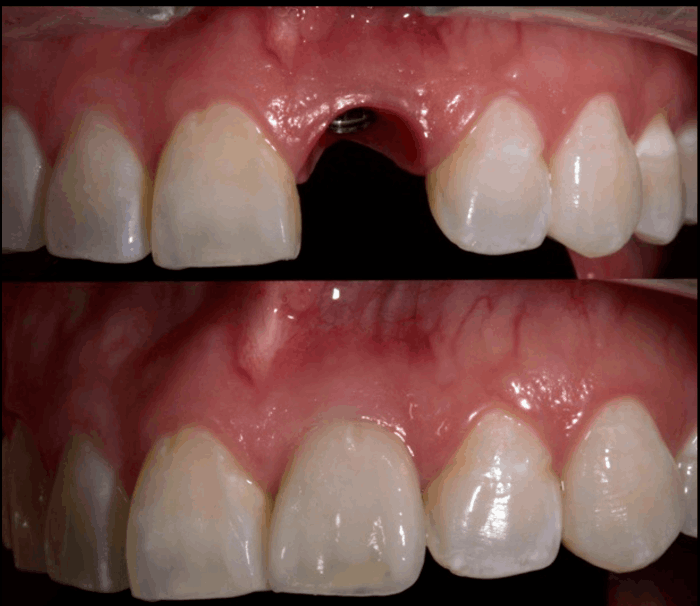

Descubre los increíbles resultados de nuestros tratamientos con esta galería de imágenes antes y después. En Bio Dental Clinic, combinamos experiencia, tecnología y atención personalizada para devolver la función, estética y confianza a cada sonrisa.